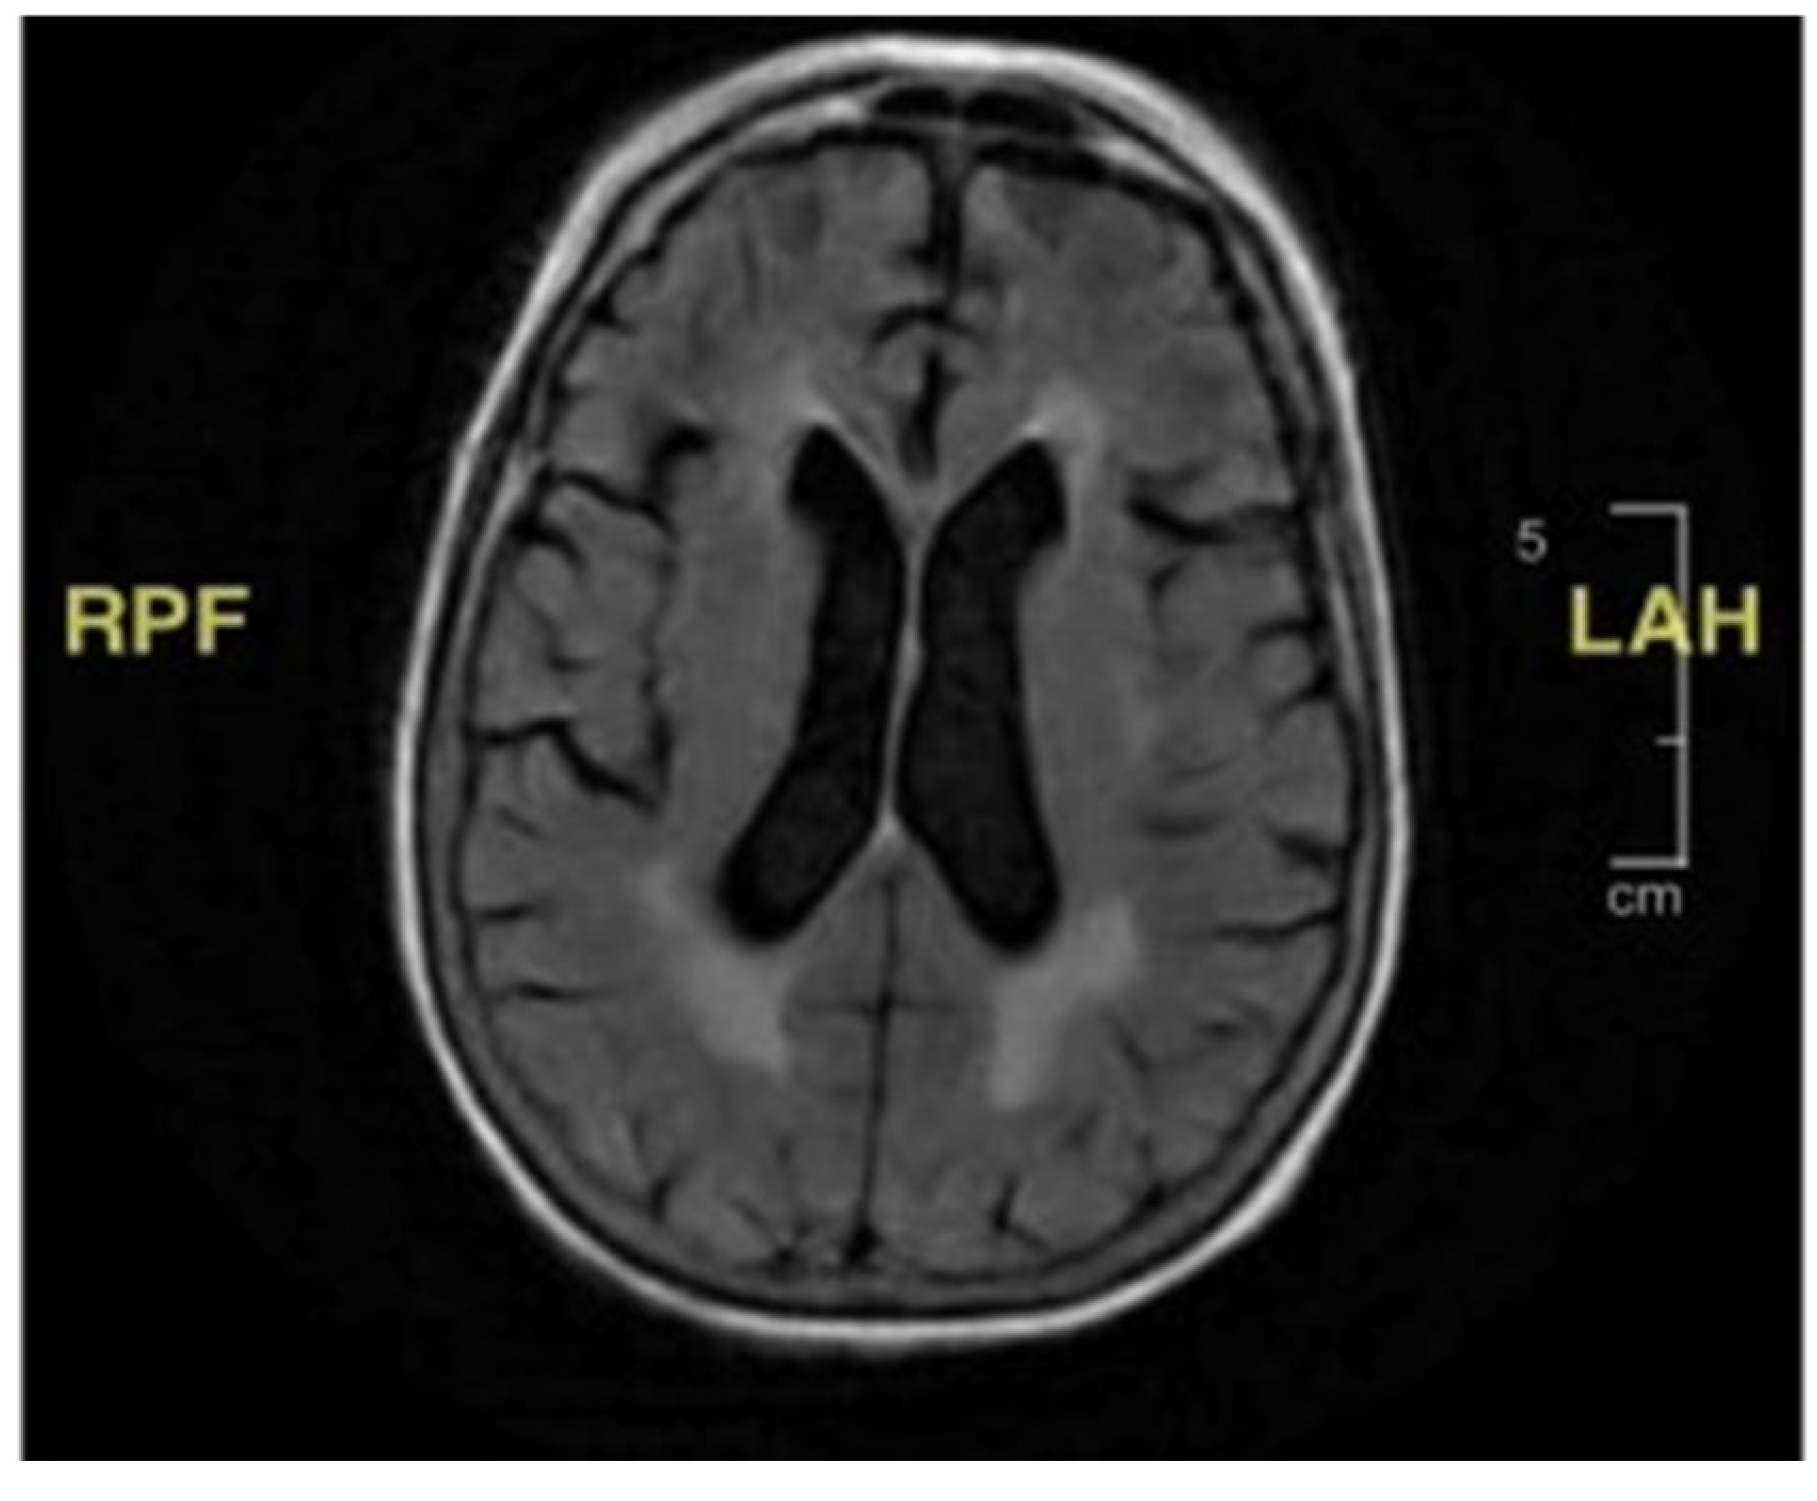

Her second hospital admission was precipitated by repeated ground-level falls from severe bilateral leg weakness. On this occasion, she described worsening back pain with ambulation. She also developed a left facial droop during the second admission. Extensive imaging, including another MRI and CT scan, showed no ischemic changes in the head and neck or acute stroke. Repeat cerebral MRI with and without contrast was negative (Figure 2). Lumbar spine MRI showed advanced degenerative disk disease but no significant pathology explaining her bilateral lower-extremity weakness (Figure 3). Lumbar spine CT showed moderate spinal stenosis at the two lowest vertebrae of the lumbar spine and a 2 mm anterolisthesis. The patient did not exhibit urinary or fecal incontinence.

Figure 2. (A,B) MRI of brain with and without contrast. White matter disease and volume loss indicating chronic microangiopathic changes. No abnormal parenchymal mass or extra-axial collection identified.